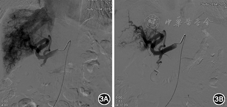

入院后经会诊于2014年12月3日行冠状动脉造影未见明显狭窄。右心导管术:外周血氧饱和度100%,上腔静脉氧71%,主肺动脉氧84%,右心房氧83%,右心室氧84%,右心室射血分数59%,肺动脉楔压15 mmHg,心输出量11.8 L/min(成年人正常值5~6 L/min),心脏指数7.7 L·min-1·m-2(成年人正常值3.0~3.5 L·min-1·m-2),左向右分流比率1.8(正常值为1.0)。鉴于患者上腔静脉和右心房血液氧饱和度相差大,且心脏指数、左向右分流比率均增高,需寻找左向右的异常分流的部位。因当时未测量下腔静脉血氧饱和度,超声与胸部血管CT检查均未发现有房室间隔缺损及异位肺静脉引流,故疑有下腔静脉异位引流。2015年4月20日上腹部血管CT未见明显粗大的肝动脉肝静脉直接相通征象,但动脉期肝静脉即显影,肝动脉及肝静脉异常增粗,符合肝动脉-肝静脉瘘(hepatic arteriovenous fistula, HAVF)(图1,图2)。经股动脉行肝血管造影见肝左动脉起自胃左动脉,胃左动脉及肝总动脉明显增粗,扭曲明显,动脉期可见肝静脉提早显影,肝内见弥漫性HAVF,以肝右动脉肝静脉瘘为主,由肝固有动脉、肝左动脉及右膈动脉供血。用无水酒精和适量明胶海绵颗粒制成的乳剂栓塞肝右动脉分支,栓塞后造影见肝右叶HAVF大部消失(图3)。术后患者偶感胸闷心悸明显,劳累后加剧,于2015年6月30日复查肝血管造影见双侧膈动脉和肝总动脉均增粗、扭曲,仍有弥漫性HAVF,由肝动脉及膈动脉供血,肠系膜上动脉造影见动脉盗血现象(图4)。分别采用浓度为25%和28%的正丁基-2-氰基丙烯酸盐进行栓塞肝右动脉两个分支,栓塞后肝右动脉肝静脉瘘消失,肝左动脉还存在动静脉分流,术后胸闷心悸症状好转。术后半年复查超声心动图示左、右心房较前明显缩小:LVEF 71%,LAD 38 mm,RAD 31 mm,LVDd 54 mm,RVDd 33 mm,肺动脉收缩压33 mmHg。术后1年复查腹部血管CT:肝动静脉瘘未见明显进展,心电图在正常范围内,胸片心影较术前缩小,心胸比0.62。在1年的随访中患者未诉明显胸闷心悸不适,稍有右上腹间断性疼痛不适,口服止痛药有效,现已很少服用。